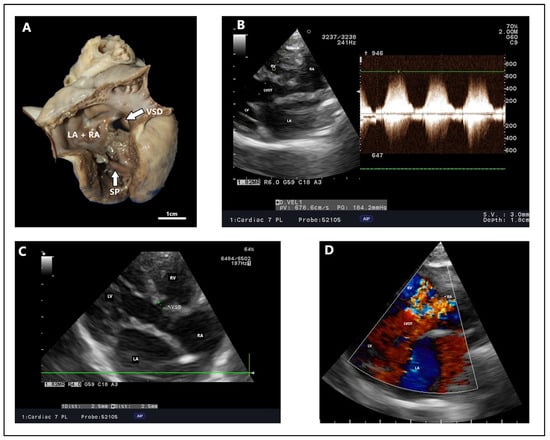

| [20] | Maine Coon | 13 | Exercise intolerance, respiratory distress, abdominal and mouth breathing, tachypnea | Perimembranous, 7.6 | 4.9 m/s | Percutaneous transcatheter closure/pulmonary artery banding | Qp:Qs 3.82, LVIDd—34.4 | Qp:Qs 2.28, volume overload, CHF after 8 months | NM | NM | Clinically normal after 8 months |

4.2. Echocardiography, Radiography, ECG Findings